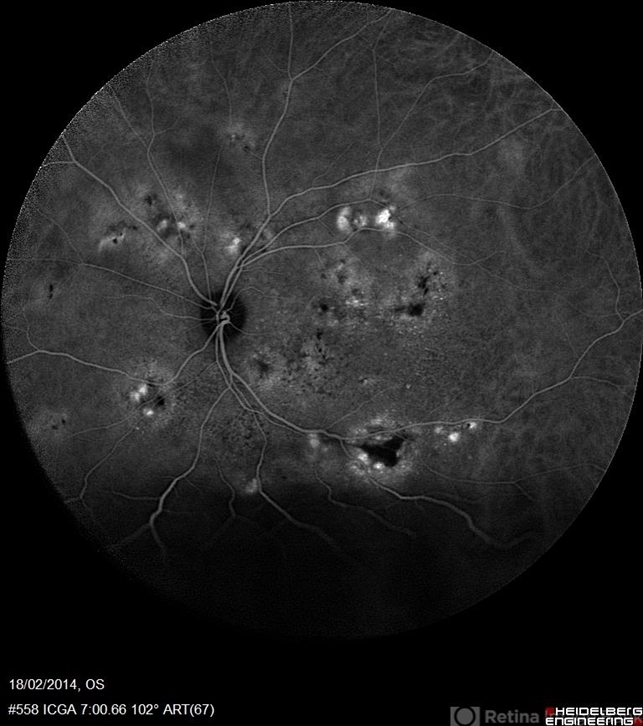

- multifocal central serous chorioretinopathy (CSCR), indocyanine green (ICG) angiography

- ICG (Late Phase) a 38-year-old man with multifocal CSR and inferior exudative retinal detachment on both eyes (Harada Syndrome) with 102 degree lens